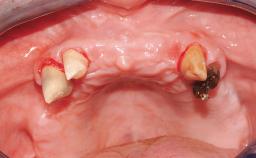

A 56-year-old female patient was referred to the clinic because of retention problems with her mandibular denture. She had been completely edentulous for more than 33 years and wore her sixth set of complete conventional dentures, which had been delivered 5 years previously. An oral surgeon had performed a vestibuloplasty in the interforaminal region of the mandible with a piece of skin tissue 12 years earlier. The panoramic radiograph and lateral cephalometric radiograph exhibited the hypotrophy of the inferior alveolar process. The mandible was a Cawood class VI,and the height of the mandible in the interforaminal zone was 15 mm.

Soft Tissue Anatomy Intact Defective

Bone Volume Horizontally and vertically sufficient Horizontally deficient Deficient vertically or deficient vertically AND horizontally